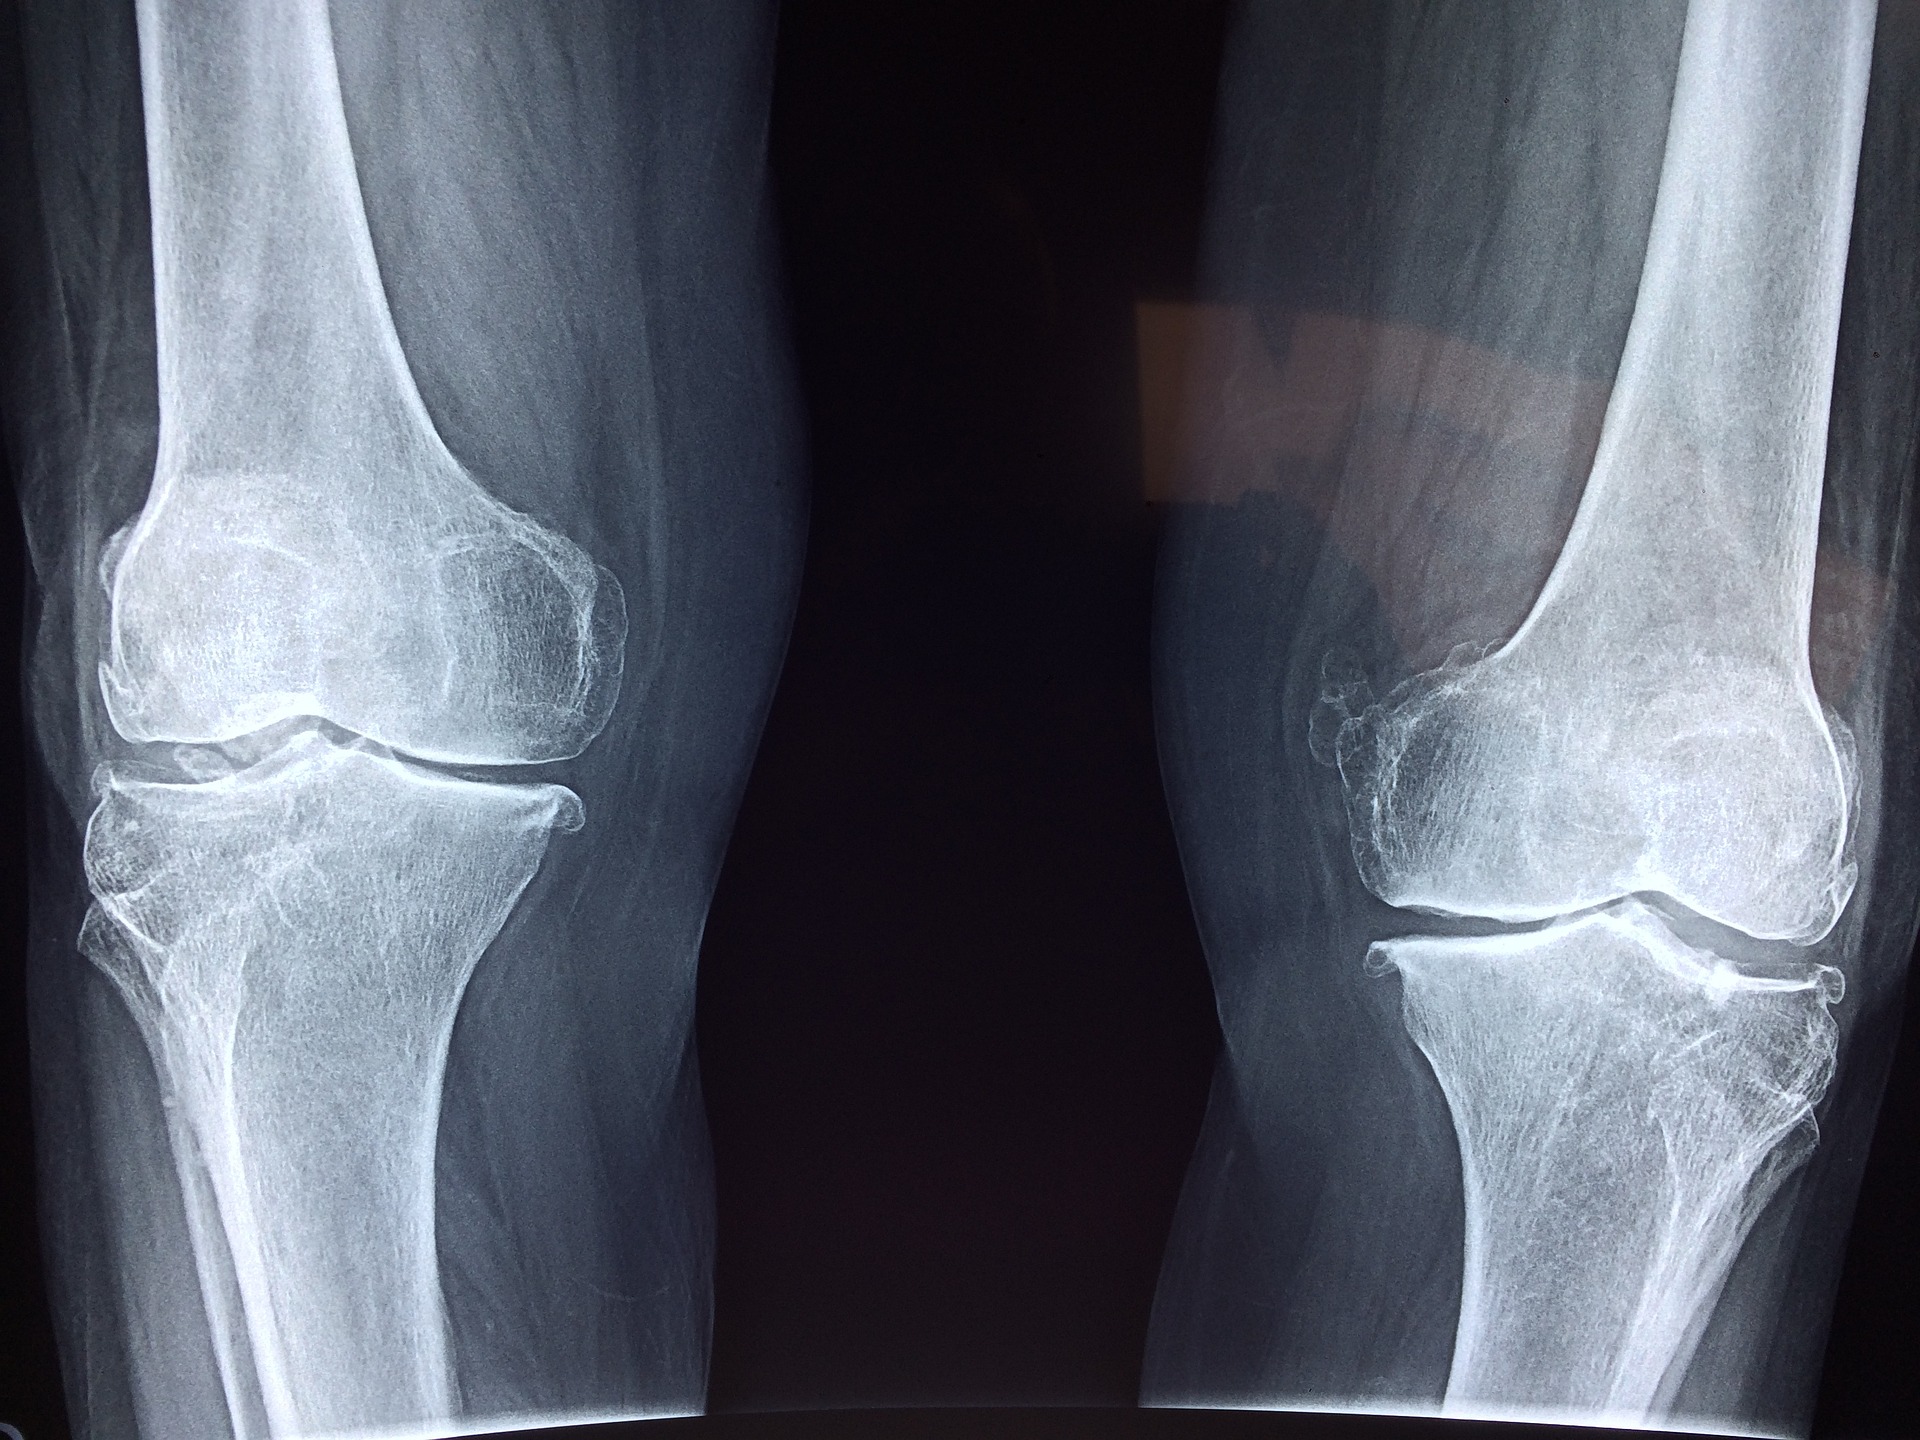

우선 콘드로이친은 그리스어로 연골이라는 뜻에서 유래됐습니다. 콘드로이친은 무릎 연골의 핵심성분으로서 연골을 구성하는 아주 중요한 성분중 하나입니다. 관절과 관절 사이에서 연골의 윤활유 작용을 하여 움직임을 부드럽게 만들어 주고 완충작용을 하여 충격을 줄여주는 역할을 합니다. 이로 인해서 우리의 뼈가 잘 움직일 수 있도록 도움을 주는 역할을 하고 있습니다. 나이가 들어가면서 연골의 주성분인 콘드로이친이 감소합니다. 이로 인해 관절사이의 마찰이 늘어나 염증이 발생됩니다. 연골의 주 성분인 콘드로이친이 줄어들게 되면 이런 증상이 발생됩니다. 무릎같은 경우는 충격을 흡수해주는 연골의 역할이 아주 큽니다. 몸의 무게를 모두 지탱하기 때문에 무릎관절의 건강을 지키는 것이 가장 중요합니다. 다리 뼈가 움직이면서 발생하는 충격을 연골이 흡수하여 무릎 관절을 보호해줍니다. 연골이 닳아서 줄어들거나 거의 사라지게 되면 움직일때마다 뼈끼리 부딪히게 되면 무릎에 엄청난 통증을 줄 뿐만 아니라 그 충격으로 인해 염증이 생길 수 있습니다. 이러한 움직임이 지속되면 퇴행성 관절염으로 이어질 수 있습니다. 연골은 60~80%가 수분으로 이루어져 있습니다. 나머지는 다양한 성분으로 구성되어 있는데 그 중 일부가 콘드로이친으로 구성되어 있습니다. 콘드로이친은 수분 다음으로 가장 많은 양을 차지합니다. 수분을 제외하고 연골의 3분의 1을 차지할 만큼 중요한 성분입니다. 연골은 평균 두께가 3mm로 매우 얇습니다. 무거운 하중을 견디다 보면 연골의 손상이 많아질 수 있기 때문에 그 건강을 지키는 것이 중요합니다.

콘드로이친은 연골에 탄성을 주는 성분입니다. 연골은 자동차의 용수철과 같이 충격을 흡수하고 완충작용을 합니다. 관절 스프링이라고 할 수 있습니다. 콘드로이친의 역할은 관절과 관절 사이에 발생하는 충격을 흡수하여 관절을 보호하고 연골의 마모 속도를 감소시킵니다. 또한 연골세포의 영양공급에도 도움을 줍니다. 뿐만아니라 연골을 포함하여 인대, 피부, 혈관 등에도 도움을 주어 좋은 효과를 기대할 수 있습니다. 콘드로이친은 수분을 끌어당기는 작용을 하여 연골의 탄력유지에도 도움을 줍니다. 이렇게 연골의 마모를 감소시키고 지켜주기 때문에 관절 간격유지에도 도움이 됩니다. 연구 결과에 따르면 2년간 콘드로이친을 섭취한 그룹과 그렇지 않은 그룹을 비교하였을때 콘드로이친을 섭취한 그룹이 관절 사이의 간격 변화가 없는것으로 유지되었다고 합니다. 또 다른 연구 결과를 살펴보면 콘드로이친을 섭취하지 않은 사람은 콘드로이친을 섭취한 사람에 비해 연골이 점점 감소하였고 연골 부피 손실률이 더 높게 나왔다고 합니다. 연골의 마모와 부피 감소를 막아 관절염으로 인한 통증을 완화시켜주는데 콘드로이친이 많은 도움이 된다고 합니다. 콘드로이친은 스스로 재생이 어려워 따로 섭취가 필요하다고 합니다. 40대가 되면 콘드로이친이 절반 이하로 감소하고 60대가 넘어가면 거의 그 수가 줄어듭니다. 이러한 콘드로이친의 변화로 인해 연골의 구조 변형이 일어나고 관절 건강이 점점 안 좋아집니다.